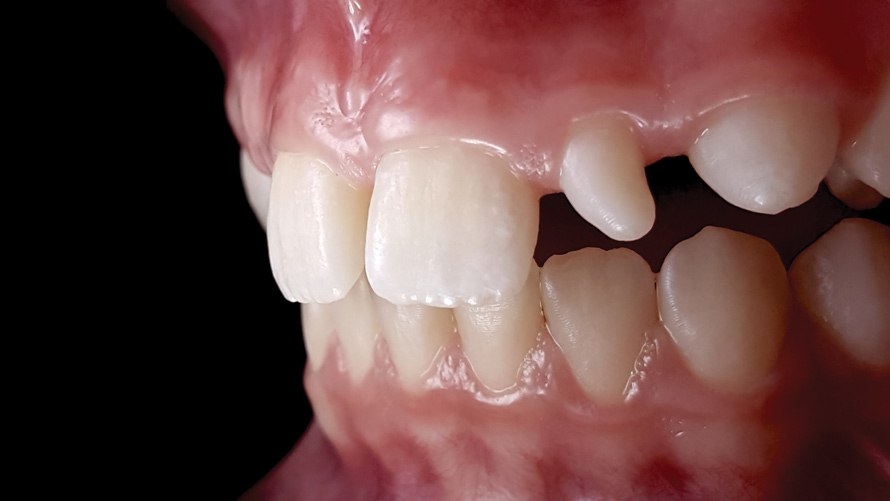

(9.) Preoperative esthetic case documentation using a smartphone and an EALS device.

Figure 9

(10.) Preoperative esthetic case documentation using a smartphone and an EALS device.

Figure 10

(11.) Preoperative esthetic case documentation using a smartphone and an EALS device.

Figure 11

(12.) Intraoral photographs taken with a smartphone and an EALS device for orthodontic evaluation.

Figure 12

(13.) Intraoral photographs taken with a smartphone and an EALS device for orthodontic evaluation.

Figure 13